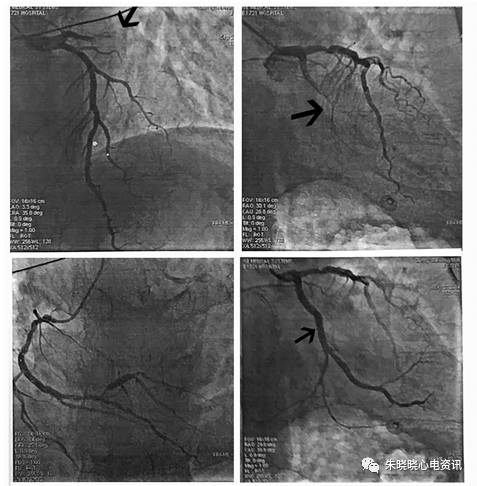

图4患者女,75岁,因“胸痛8小时”入院。

发现血压高3年。查体:血压145/90mmHg;神清,双肺呼吸音粗,双下肺闻及细湿罗音,未闻及干罗音,心率104次/分,心律绝对不齐,第一心音强弱不等,未闻及病理性杂音。入院心电图示:心房颤动,临时起搏。V1-V6呈R型,I、aVL和V7-9导联(第一个自身的QRS波群)显示出ST段抬高0.05-0.1mV。Ⅱ、Ⅲ、aVF导联ST段压低0.05-0.1mv,V1-6导联ST段压低0.1-0.3mV。冠状动脉造影显示回旋支近段完全闭塞(箭头指示)。